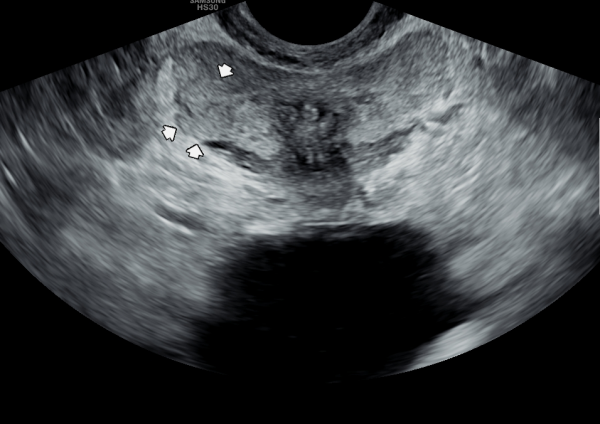

내원 첫날 정면 경직장 전립선 초음파 정낭의 검사상 사정관 입구의 순환 장애로 정낭의 낭종이 관찰되는 초음파 사진입니다.

This is a transrectal prostate ultrasound image taken on the first visit, showing a cyst in the seminal vesicle caused by a circulation blockage at the entrance of the ejaculatory duct.

4개월 가량 주 2회 정낭의 표적 치료후 정낭의 낭종들이 감소하고 순환되는 추적 경직장 전립선 초음파 사진입니다.

This is a follow-up transrectal prostate ultrasound image taken after approximately four months of twice-weekly targeted treatment of the seminal vesicles. The image shows that the cysts in the seminal vesicles have decreased and circulation has improved.

주 2회 전립선과 사정관과 정관 그리고 정낭 등의 표적 치료후 정낭 낭종들이 치료된 경직장 전립선 초음파 사진입니다.

This is a transrectal prostate ultrasound image showing that, after targeted treatment of the prostate, ejaculatory ducts, vas deferens, and seminal vesicles twice a week, the seminal vesicle cysts have been successfully treated.